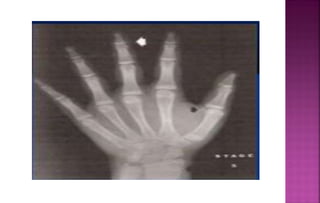

Eleven discrete adolescent SMI covering the entire period of

adolescent development have been described .

Epiphysis as width as diaphysis;-

SMI I;- Third finger – Proximal phalanx(PP3)

SMI II;- Third finger – Middle Phalanx(MP3)

SMI III;- Fifth finger - Middle Phalanx(MP5)

Ossification;-

SMI IV;- Appearance of Adductor Sesamoid of

Thumb(4S)

Capping of Epiphysis ;-

SMI V ;- Third finger – distal phalanx(DP3 CAP)

SMI VI;- Third Finger– middle phalanx(MP3 CAP)

SMI VII;- Fifth Finger-middle phalanx (MP5 CAP)

 Fusion of epiphysis and diaphysis ;-

SMI VIII- Third finger- distal phalanx(DP3U)

SMI IX- Third finger- proximal phalanx(PP3)

SMI X- Third finger- middle phalanx(MP3u)

SMI XI- Radius(Ru)